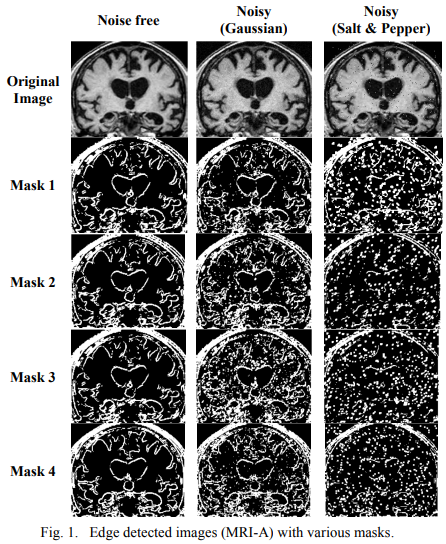

Comparative study of fractional filters for Alzheimer disease detection on MRI images

This paper presents a comparative study of four fractional order filters used for edge detection. The noise performance of these filters is analyzed upon the addition of random Gaussian noise, as well as the addition of salt and pepper noise. The peak signal to noise ratio (PSNR) of the detected images is numerically compared. The mean square error (MSE) of the detected images as well as the